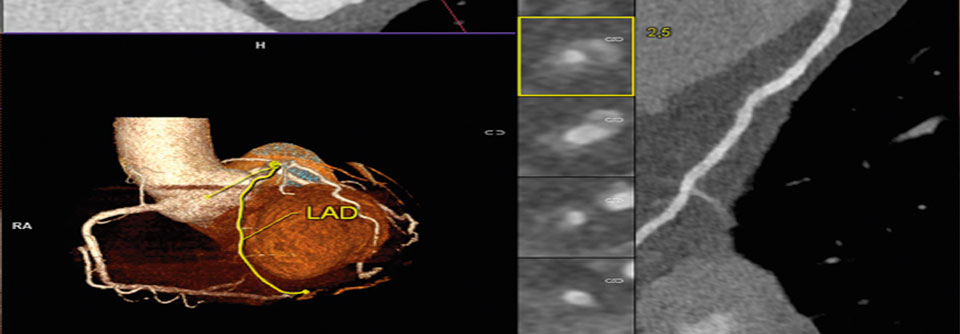

Geringe Strahlenbelastung, kein eingeführter Fremdkörper, kurze Untersuchungszeit: Das CT der Koronarien klingt vor allem für Patienten nach einer verlockenden Alternative zum Katheter. Doch welchen Stellenwert hat es wirklich?

Eine größere Studie mit 230 Patienten aus 16 Zentren ergab für das Kardio-CT eine Sensitivität von 95 % und eine Spezifität von 83 %. Allerdings litten auch nur 14 % der Teilnehmer an einer KHK, es handelte sich also um ein eher gesundes Kollektiv, betonte Privatdozent Dr. Andreas Rolf von der Kardiologie am Herzzentrum der Kerckhoff-Klinik in Bad Nauheim.

An einem etwas größeren Kollektiv mit einer KHK-Prävalenz von 68 % fand sich dann eine Sensitivität von 99 % und eine Spezifität von 64 %. „Wir übersehen die Krankheit mit dem CT also nicht, aber am anderen Ende der Erkrankung, bei schwer veränderten Gefäßen mit viel Kalk, liegen…